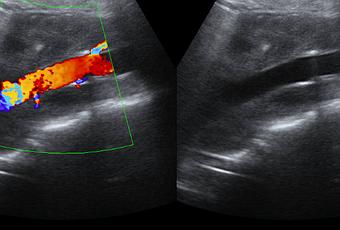

POR MEDIO PARTICULAR SE SOLICITA USG ABDOMINAL COMO ABORDAJE INICIAL. MOSTRANDO MASA RETROPERITONEAL DE GRAN TAMAÑO DE HASTA 14.7 CM, HIPOECOICA RESPECTO A LA GRASA ABDOMINAL, DE BORDES DEFINIDOS, QUE ENVUELVE LOS VASOS ABDOMINALES SIN COMPRIMIRLOS, QUE A LA EXPLORACIÓN CON DOPPLER COLOR QUE NO MUESTRA VASCULARIDAD.